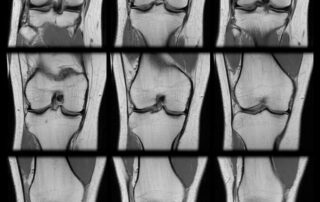

ACL Tear Diagnosis: When Do You Need a Knee MRI?

Navigating an anterior cruciate ligament injury often begins with a knee MRI to confirm the diagnosis. A sudden popping sound followed by intense pain can [...]